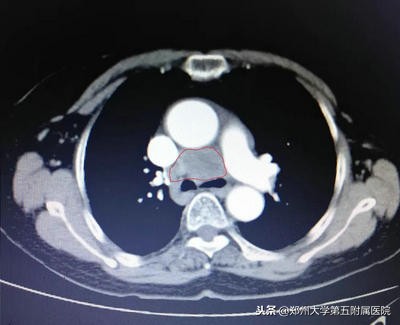

▲ 纵膈占位伽玛刀治疗前和伽玛刀治疗后对比,肿块明显缩小,压迫症状好转